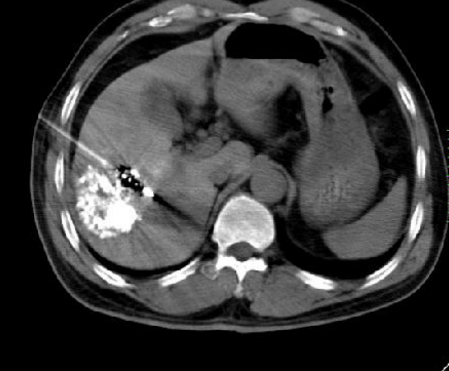

肝癌微创介入治疗 核磁复查提示效果好